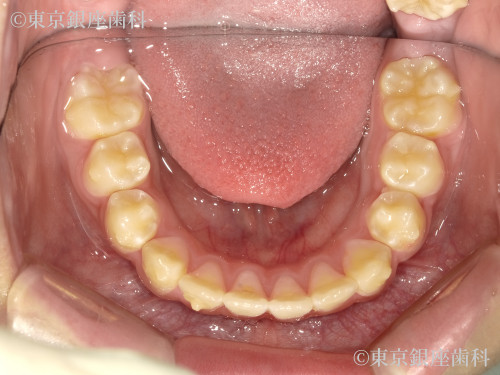

Before

10代 女性

疾患 矯正

施術内容 矯正

治療期間 11ヶ月 費用 65万円(税込)

インビザライン:ファースト